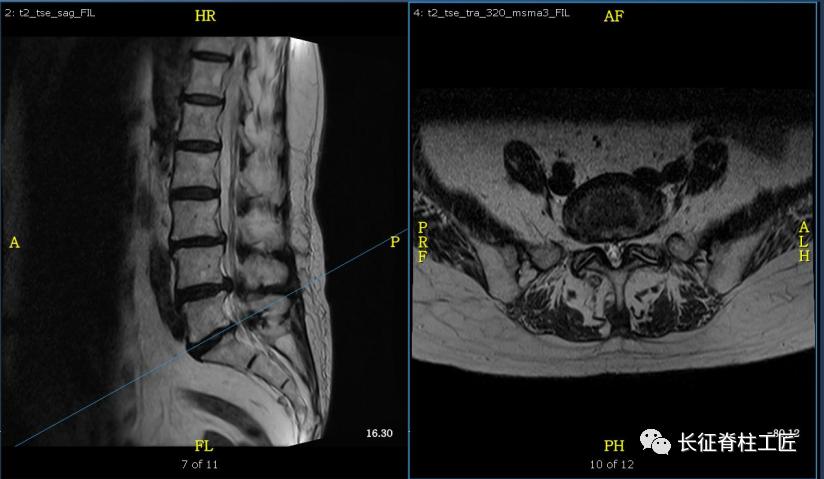

入院检查,腰部疼痛,后伸时加剧,局部压痛,双下肢肌力减退。X线检查,L4、L5骨质增生,MRI显示L4/L5、L5/S1椎间盘突出,马尾神经受压明显,被确诊为腰椎管狭窄症。

脊柱外科史国栋主任带领团队详细讨论,决定行椎管减压植骨融合内固定术。秉持微创的理念,术中通过精确的切口设计、肌肉组织的保护、手术时间的控制、后侧韧带复合体的保留等措施,在开放的手术中微创的完成了手术。